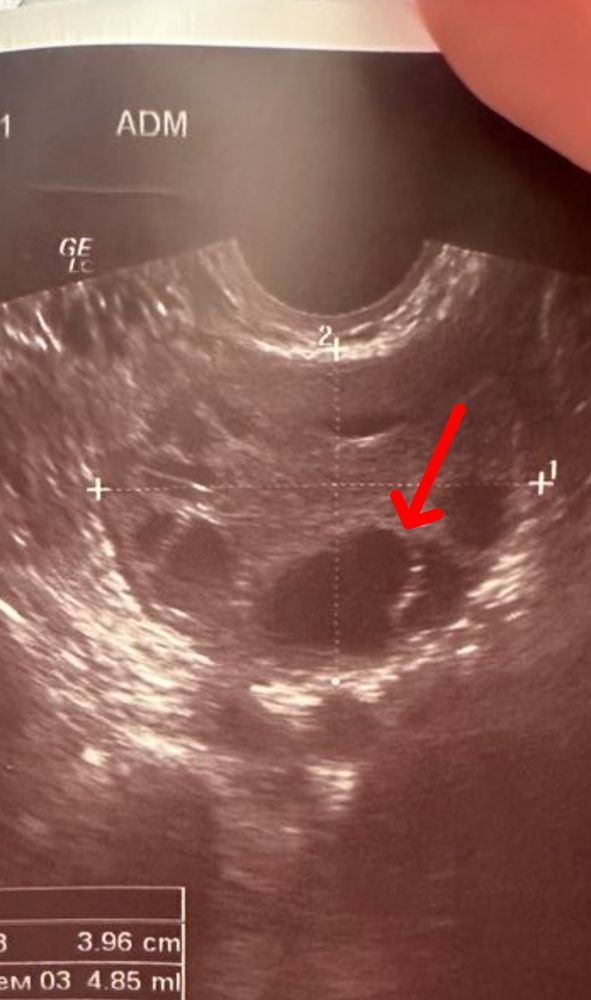

An, если приглядеться и это не помеха экрана, то вроде ещё видно ЯК на выходе. Изображение

An, я вижу ДФ в момент овуляции. Яйценосный бугорок уже лопнул и ДФ сдулся, ЯК уже вышла буквально вот вот либо в процессе выхода

Узи фолликулометрия Овуляция? Дф? Или желтое тело?